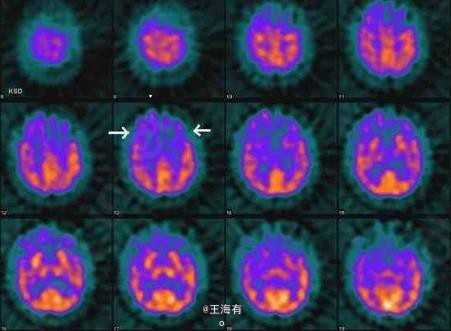

49岁,男,进行性行为改变入院

进行性智能减退,记忆障碍明显

Pick病 处理 此病暂无有效疗法

Pick病是一种罕见的进行性变性疾病,大多累及额叶和颞叶。预后本病预后不良。常在发病1年内迅速转入痴呆